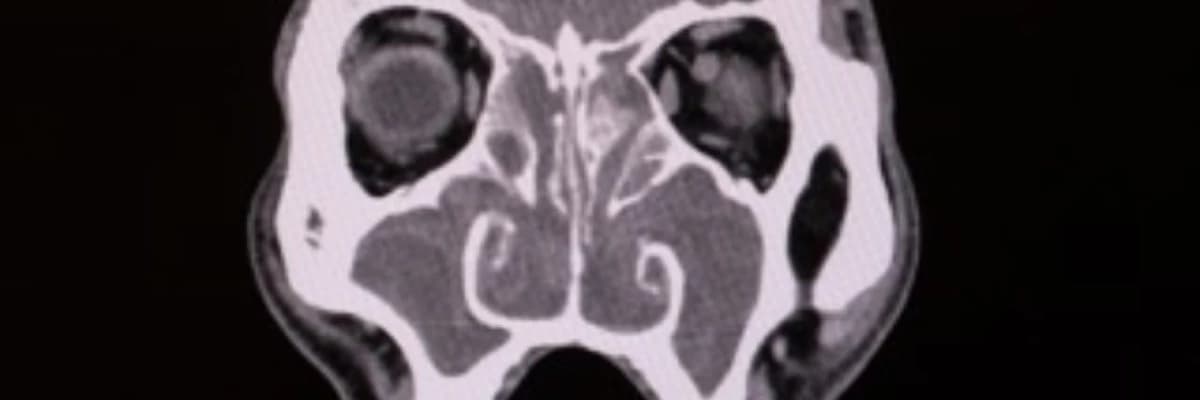

Tıbbi literatür verilerine göre, gribal enfeksiyonlar sırasında çekilen tomografilerde (BT) sinüslerde geçici anormallikler görülebilir; ancak bunlar genellikle 2-3 haftada kendiliğinden düzelir. Eğer şikayetleriniz 12 haftalık süreyi geçtiyse, uzman bir KBB hekimi şu yöntemlerle kesin teşhisi koymaktadır:

- BT (Tomografi): Sinüslerdeki kronik tıkanıklığın ve olası poliplerin kesin tespiti.